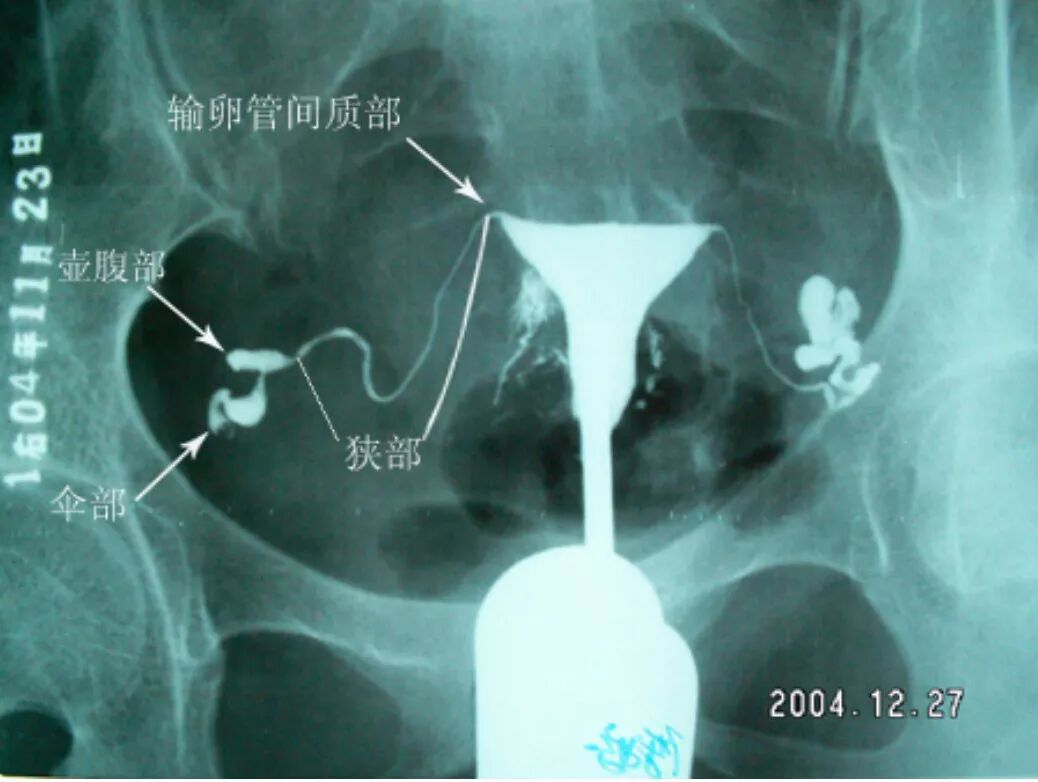

正常子宫---输卵管造影表现

子宫输卵管造影图解

输卵管造影片子图解

子宫输卵管造影解剖图

输卵管造影片子讲解图